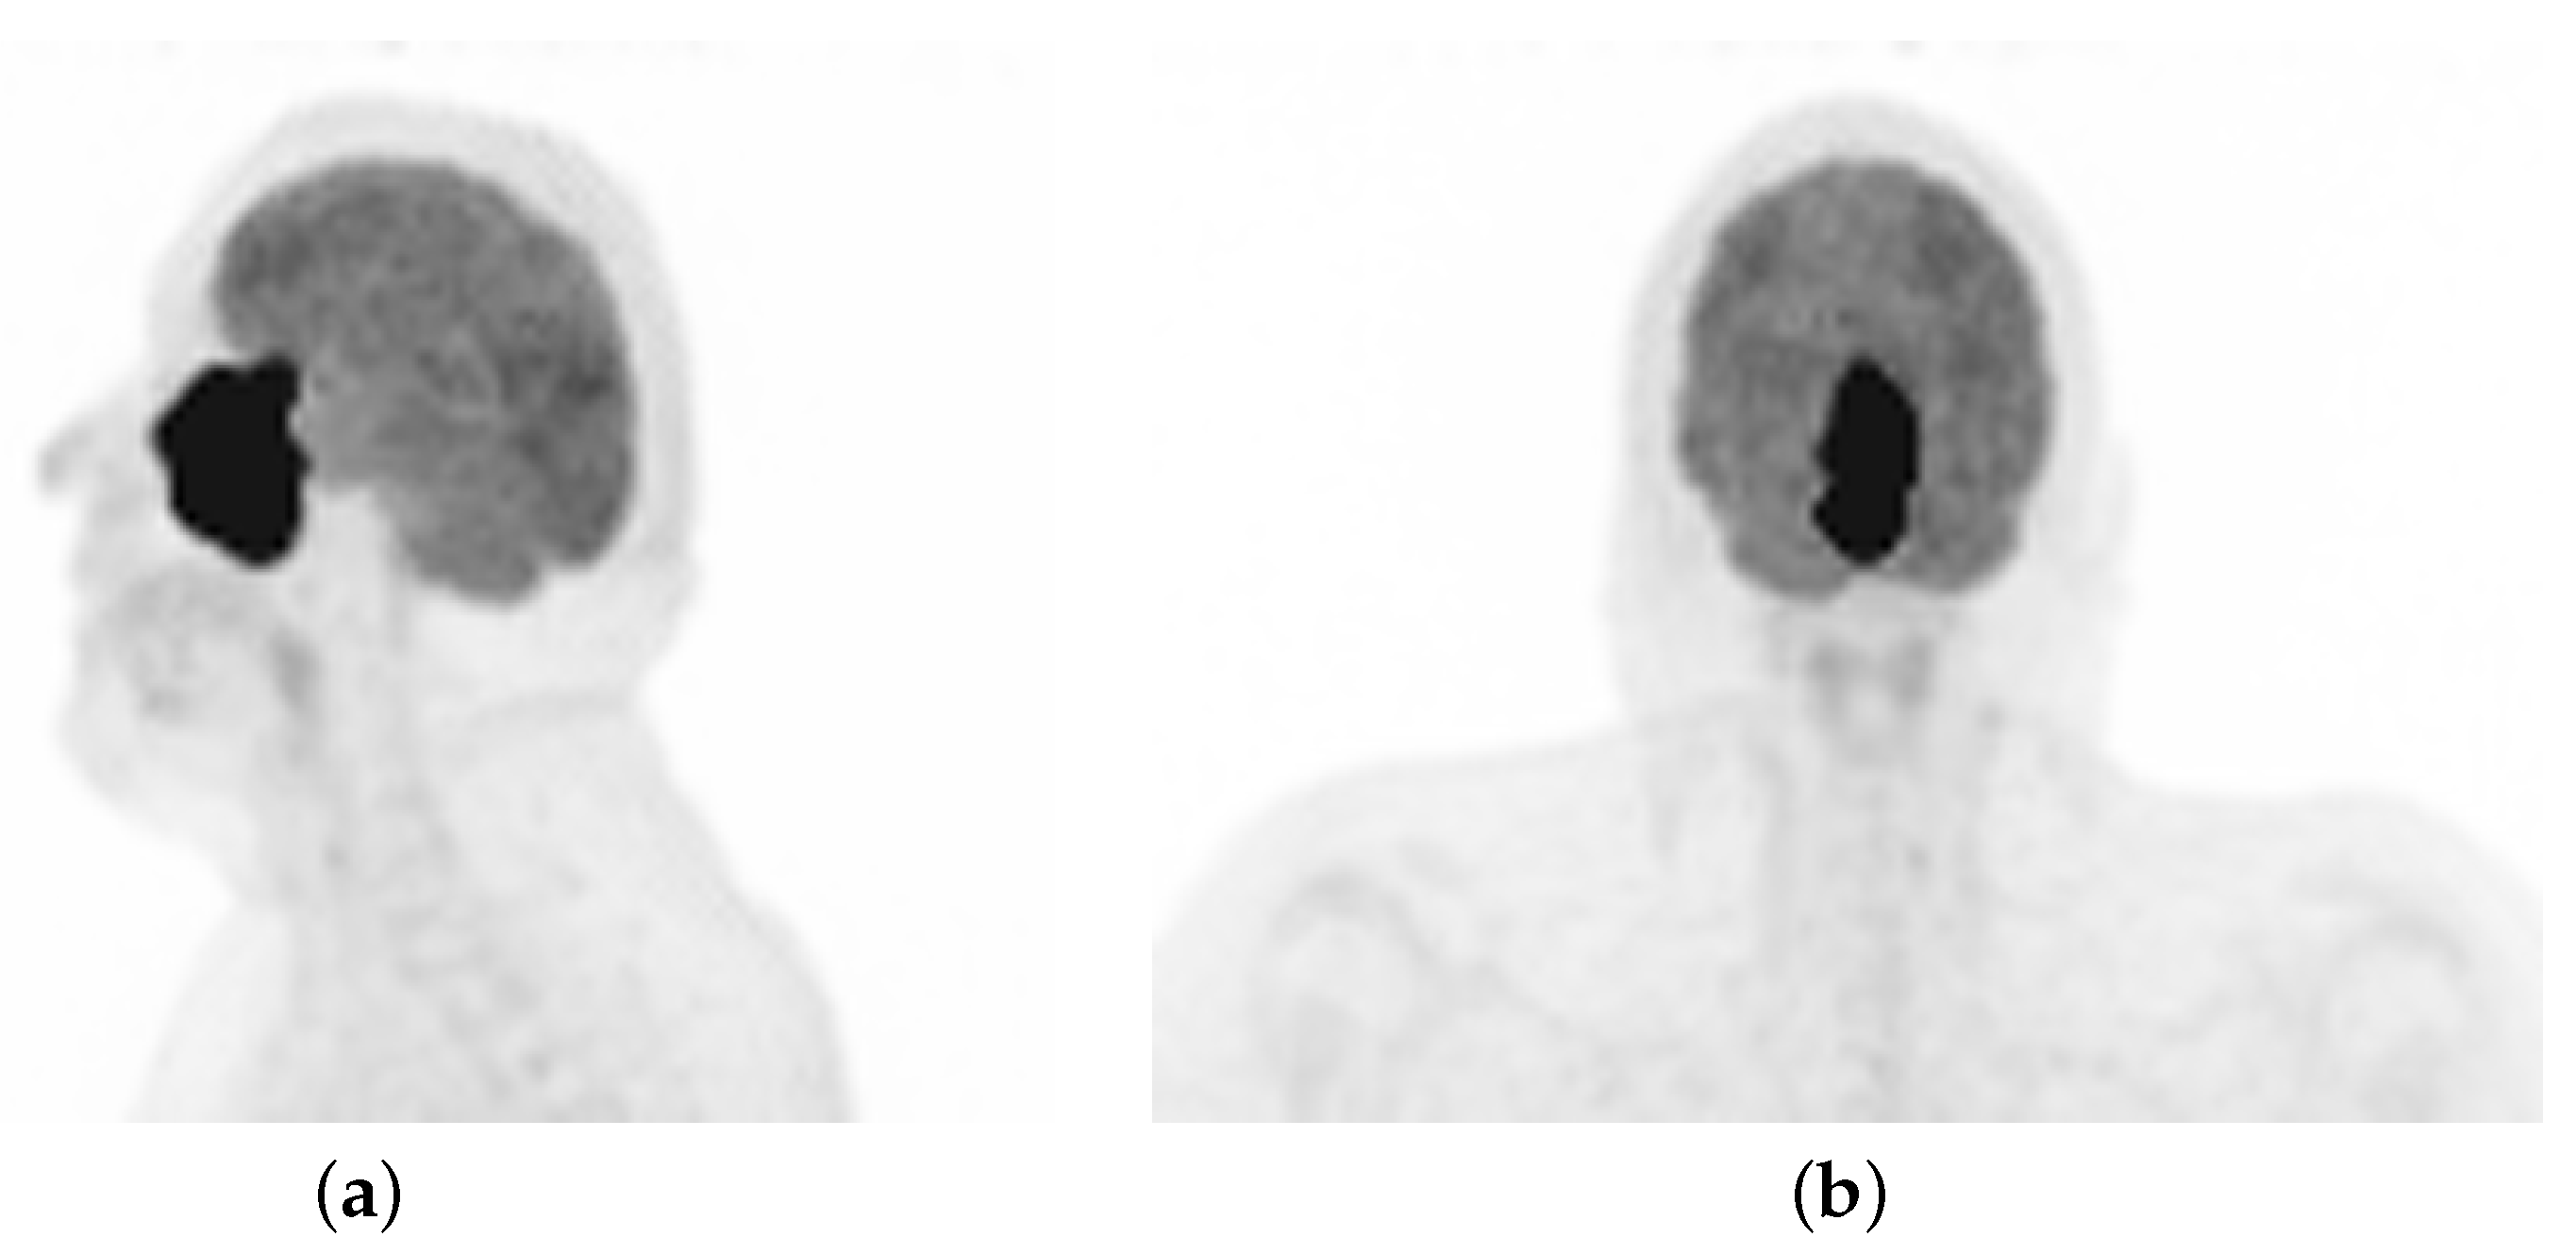

| PET | Positron emission tomography |